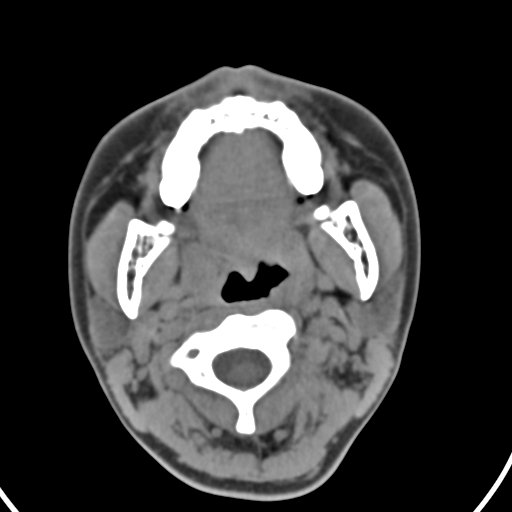

以下是引用zjzjr在2008-12-5 11:46:00的发言:[br]脂肪密度,壁有钙化.考虑口咽部皮样囊肿可能性大.双侧上颌窦炎,双侧下鼻甲粘膜肥厚.增殖腺肥大,扁桃体亦增大,考虑炎性.

以下是引用随光逐影在2008-12-5 18:27:00的发言:[br]1)考虑左侧茎突过长综合征并茎突舌骨韧带囊肿形成突入咽部;左侧咽部慢性炎症。2)鼻咽腺样体肥大。3)双侧扁桃体肿大。4)双侧上颌窦炎。5)双侧下鼻甲粘膜肥厚。